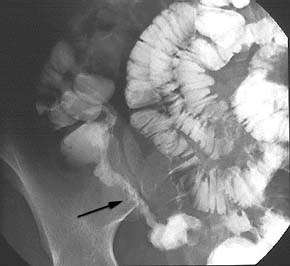

La réalisation d’un entéro-scanner ou d’un transit baryté du grêle permettra de visualiser une atteinte de l’intestin grêle en particulier une sténose. La vidéocapsule à son indication dans la recherche d’atteinte du grêle mais est contre-indiquée s’il existe une sténose d’où l’intérêt de rechercher celle-ci par un examen radiologique initialement.

Figure n° 4 : Sténose (Flèche) de l'iléon sur un transit du grêle

(Source Klinikmanual.de)